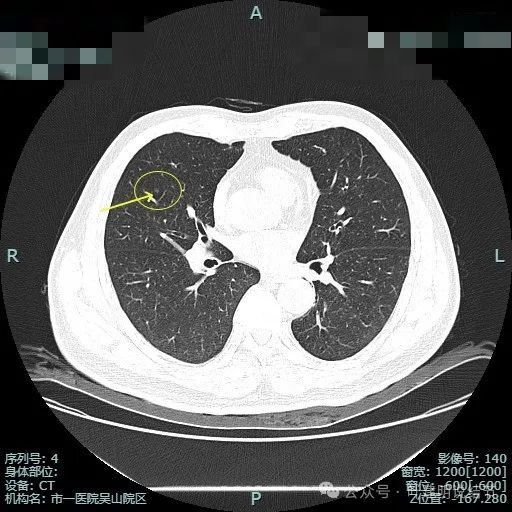

右上叶另有病灶B:微小淡磨,轮廓较清。

右肺另有微小实性结节,病灶C,考虑良性。

左下叶少许斑片状影,轮廓欠清,少许慢性炎或伴纤维增生或肺泡上皮增生。